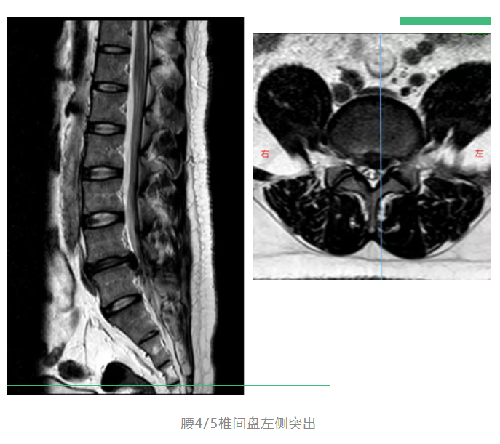

终于来到深圳市中医院就诊。曹主任先帮我做了详细的体格检查,然后让我做CT看看情况。 没想到CT报告提示腰椎间盘脱出(说明腰椎间盘突出的程度明显比以前加重了),而且突出的很大一部分掉到了椎管里。

椎管是脊柱上的一条骨性通道,里面通行着脊髓,而脊髓则是直接连接着大脑的一条神经主干,全身肢体上的所有神经基本都是由脊髓分出来的。椎间盘突出,特别是较大的突出,很容易造成神经的压迫,从而引起症状。

曹主任根据体格检查和CT报告,耐心地帮我分析病情:

从片子上看,腰部的椎间盘突出比较严重,腰部神经受到了影响,出现了明显的症状,严重影响生活,片子表现跟临床表现相符合,因此诊断十分明确。